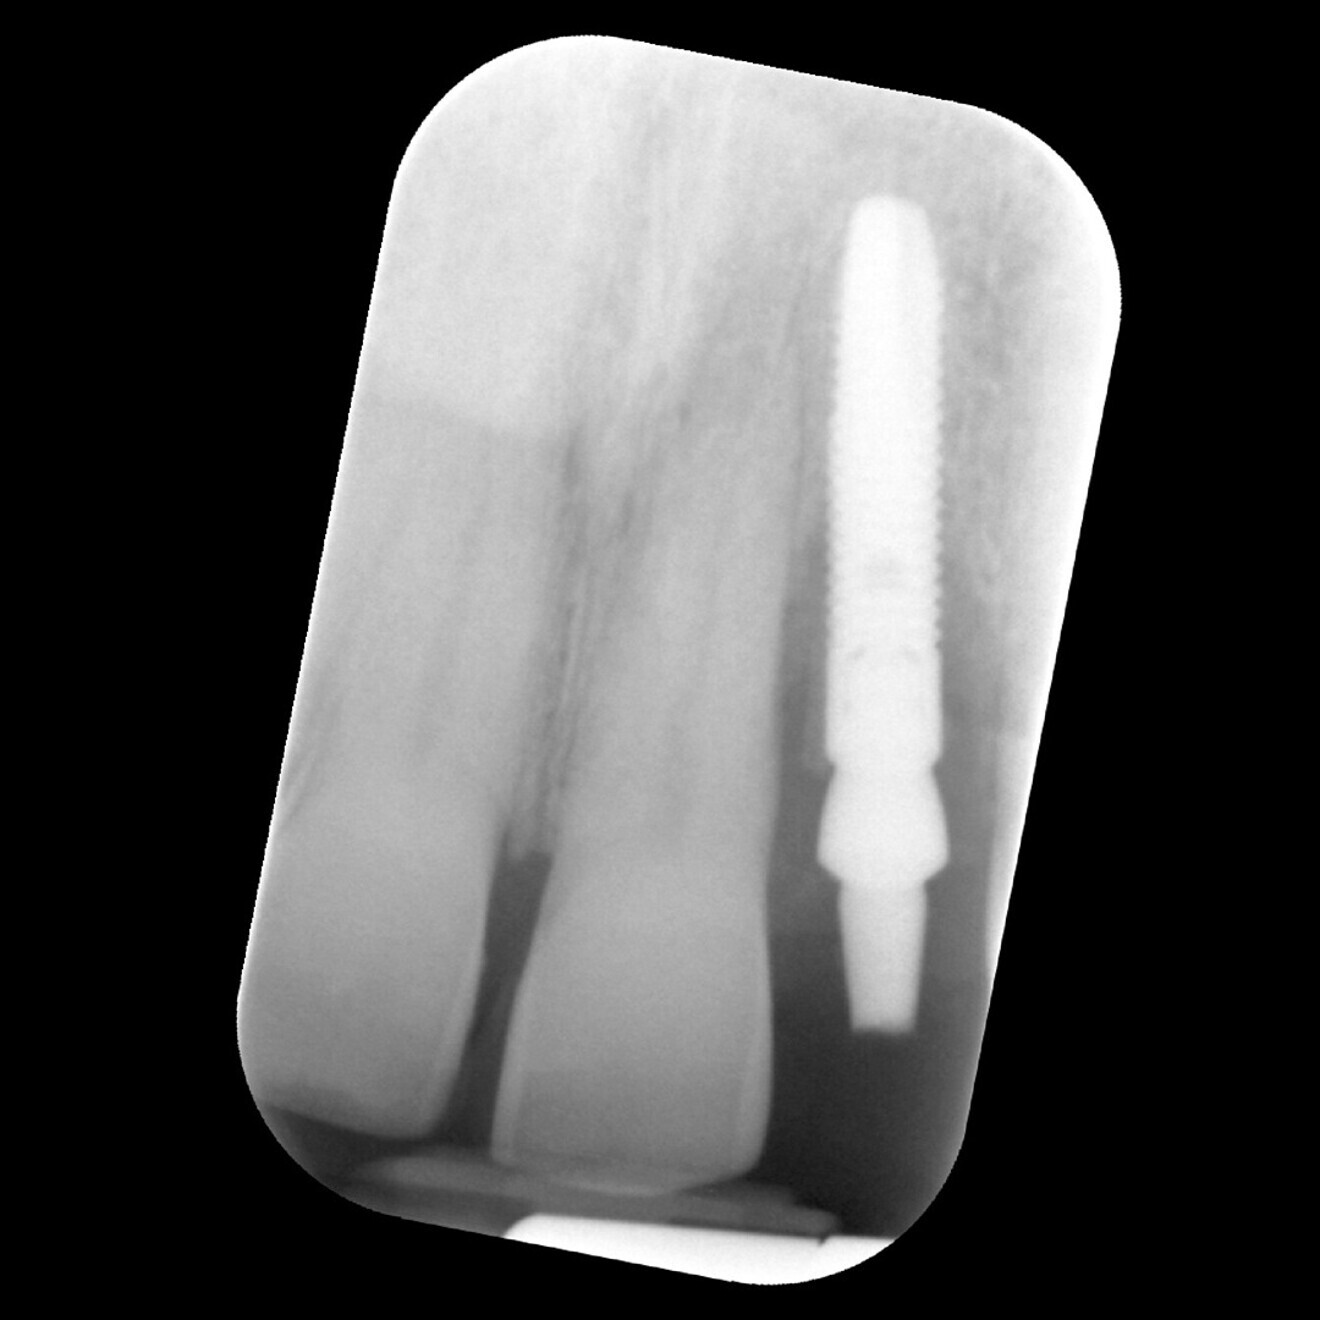

Fig. 13: Radiograph of the implant at baseline insertion of the definitive crown.

At this stage, impressions were taken using an intra-oral scanner, and the definitive screw-retained crown was fabricated utilising an Atlantis CAD/CAM abutment (Dentsply Sirona) and a bonded zirconia crown (Fig. 12). RFA was performed again at nine months and one year after placement, resulting in further increases to 85/84 ISQ and 86/86 ISQ, respectively. This plateauing of the ISQ values indicated that the graft had matured and complete secondary stability had been achieved. Thus, at the 12-month follow-up, not only was the patient satisfied with the aesthetics of the fixed restoration, including the enhanced soft-tissue profile, and the favourable radiographic outcome (Fig. 13), but we also gained insightful and detailed information on implant stability from the longitudinal ISQ values, giving us confidence in the long-term prognosis of this implant-supported restoration.